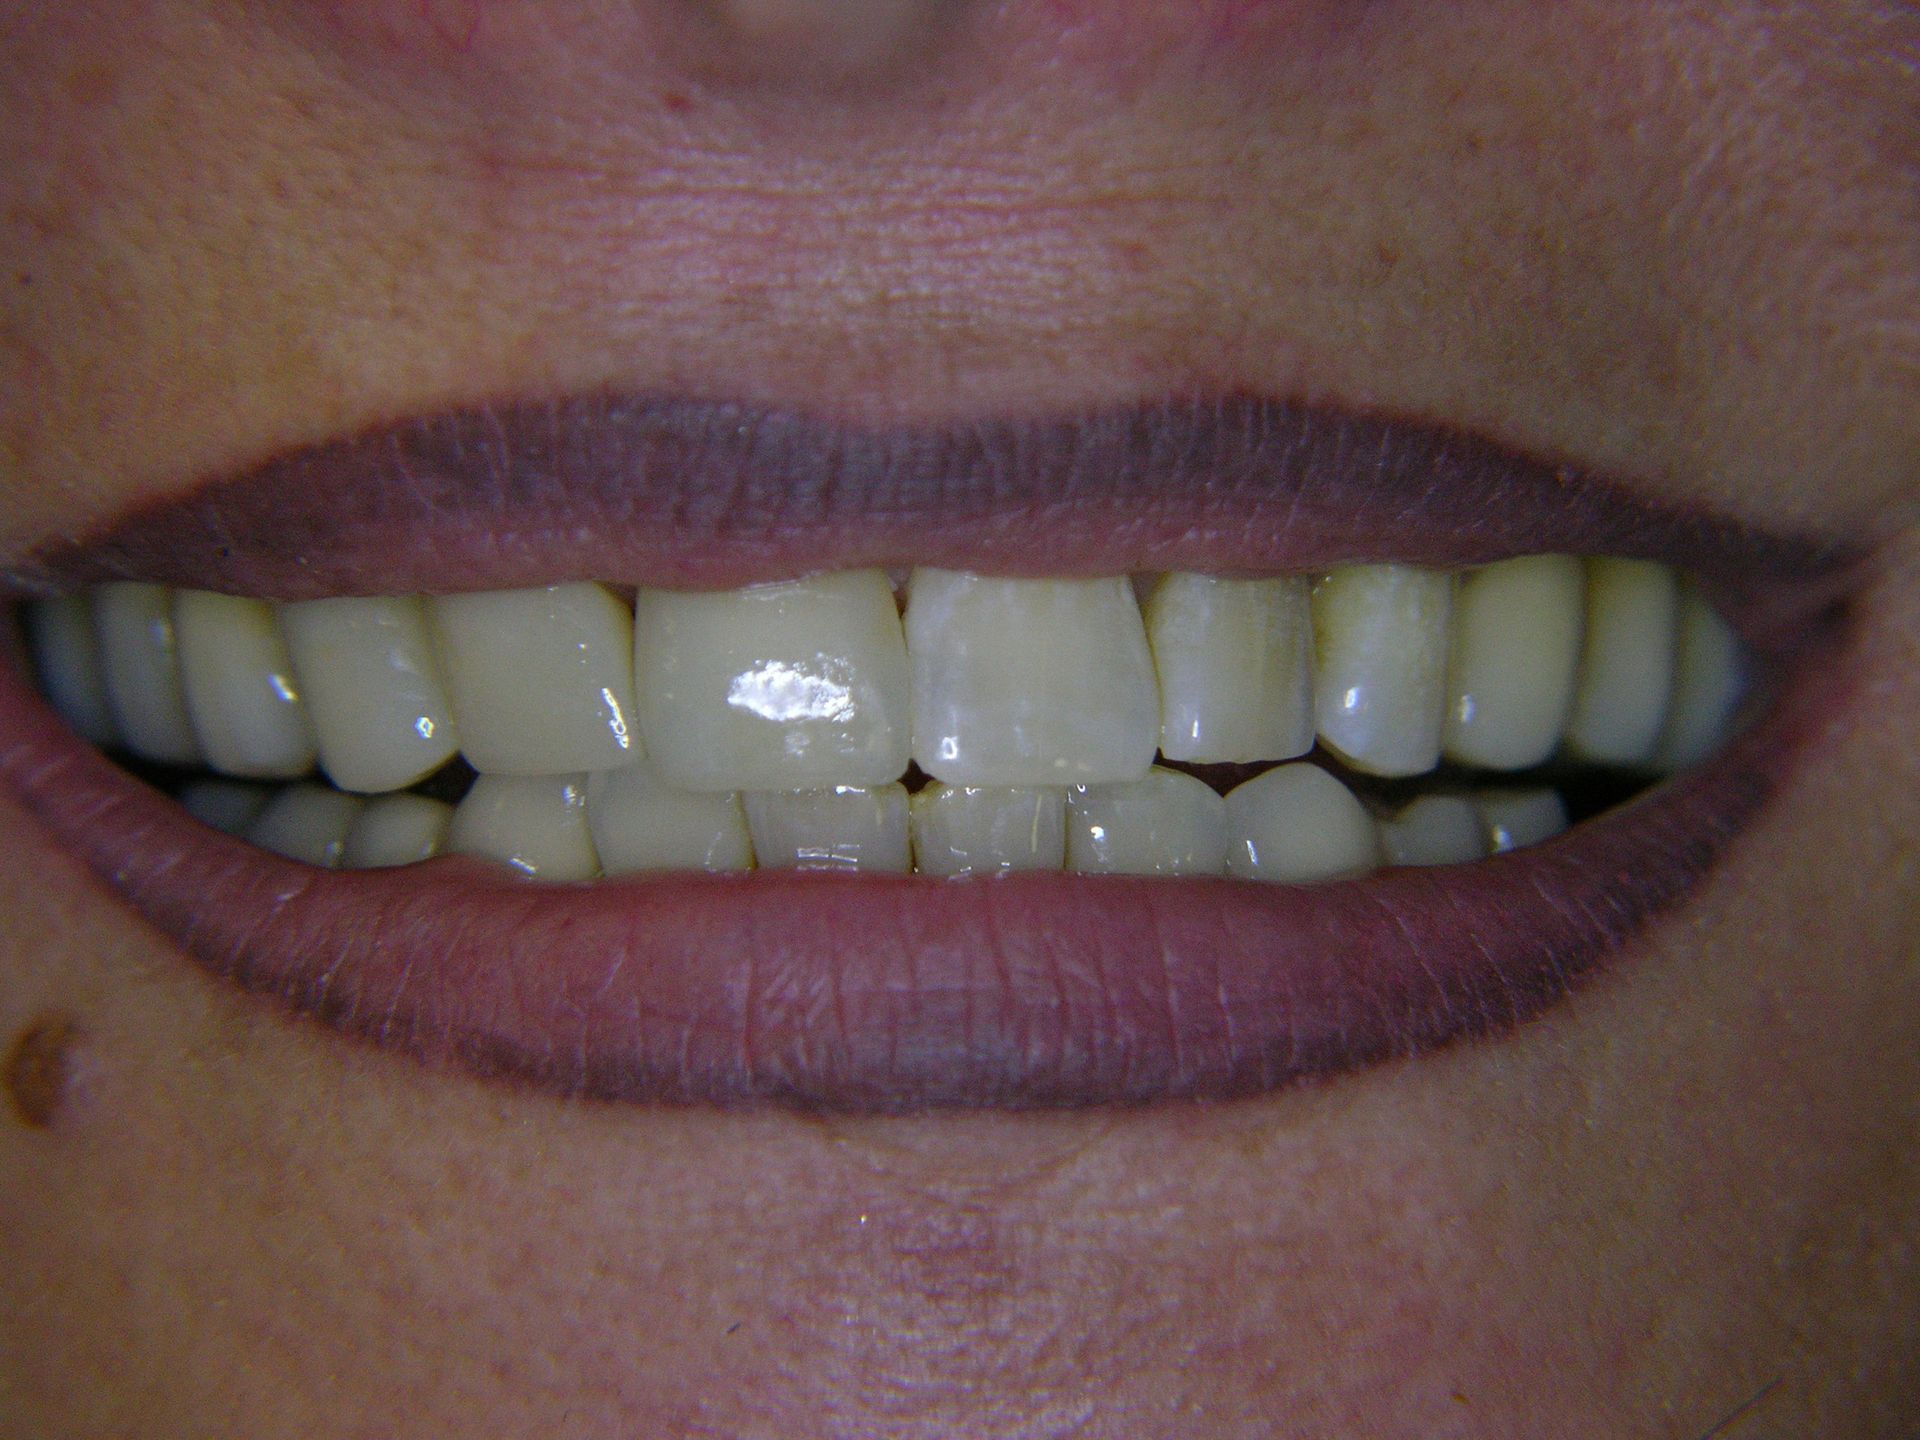

Beispiele von Versorgungen